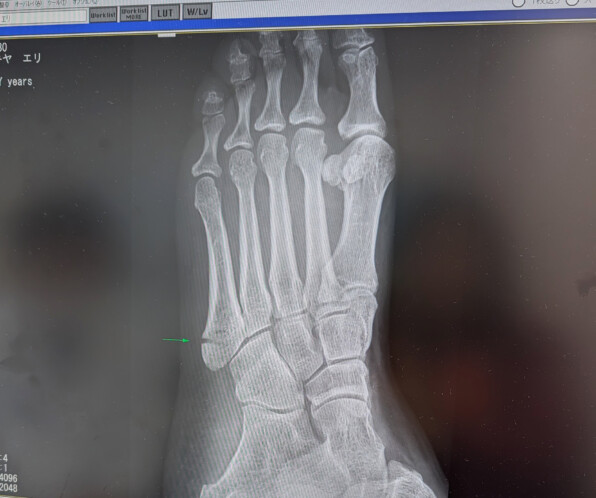

●4週間と3日間、文字通りの「足かせ」であった、

ギプスが取れましたー✨️✨️